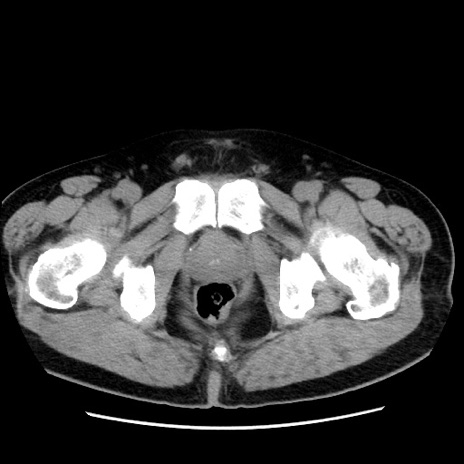

症例16(横断像)

【症例】 70歳代男性

【主訴】 腹痛、嘔吐

【現病歴】 約1ヶ月前より間欠的に腹痛と嘔吐あり、当院消化器内科を受診したところCTで多発する肝臓のLDAを指摘され、精査中であった。以降は消化器症状は安定していたが、2日前より嘔気と腹痛があり、同日より排便・排ガスが消失した。改善認めず、 本日、救急外来を受診した。

【既往歴】 大腸ポリープ切除後。

【身体所見】意識清明・会話良好、BT 36.3℃、BP 127/80mmHg、 P 80bpm、腹部:膨満あり、平坦・軟、上腹部正中および下腹部正中に圧痛あり、反跳痛なし、筋性防御なし。

【データ】WBC 7200、CRP 0.77